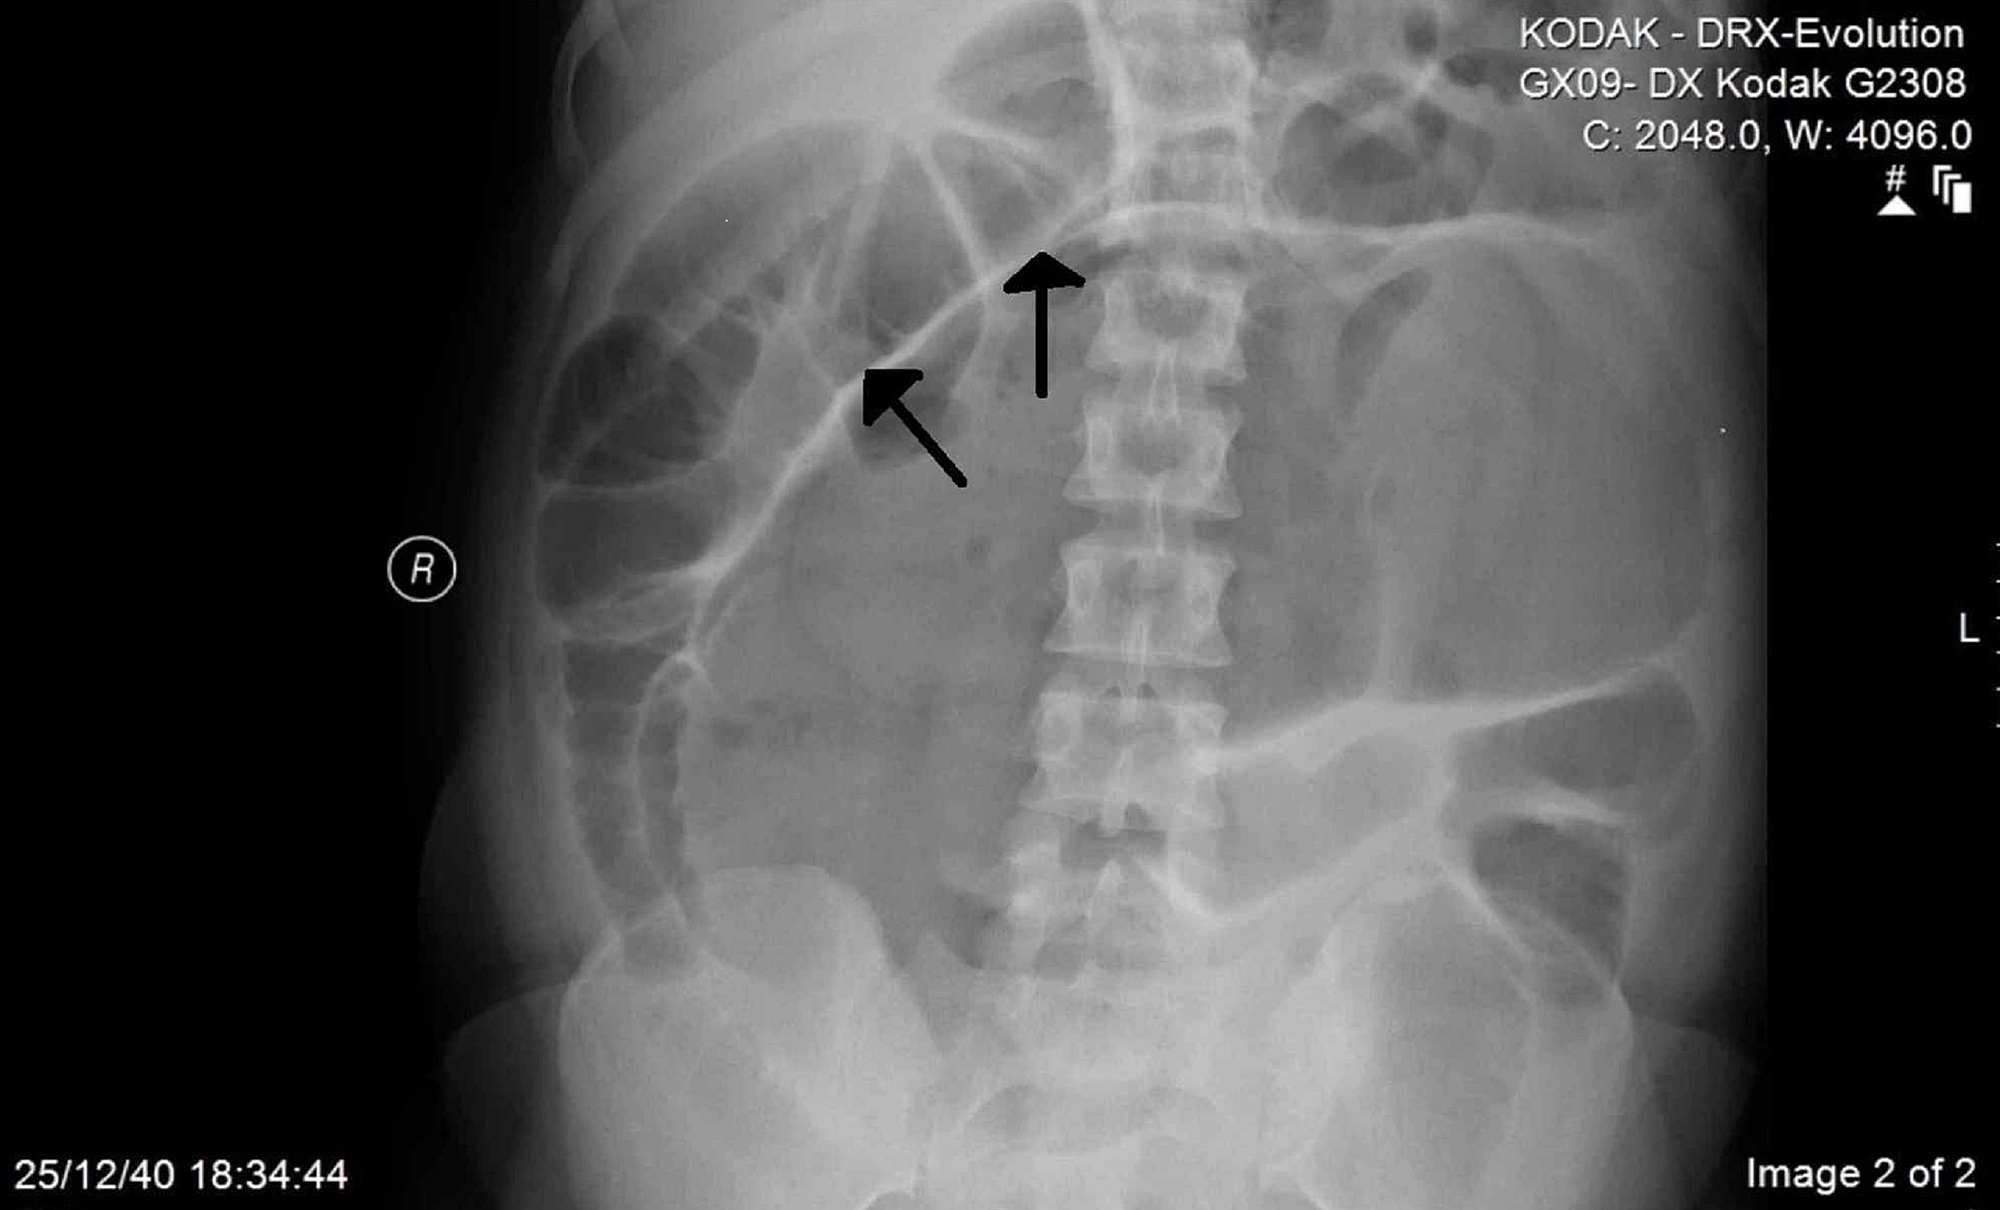

Cecum volvulus is a rare from of the intestinal obstruction. Radiologically, it appears as embryo-like structure. The patient may present with acute abdominal pain and discomfort. Abdominal distension, nausea, and vomiting are other common complaints. Cecal volvulus is treated surgically via cecopexy. If gut is damaged irreversibly, intestinal resection may be done. Reference: https://www.healthline.com/health/cecal-volvulus#treatment Image via: https://www.cureus.com/articles/26408-cecal-volvulus-post-cesarean-section-a-case-report